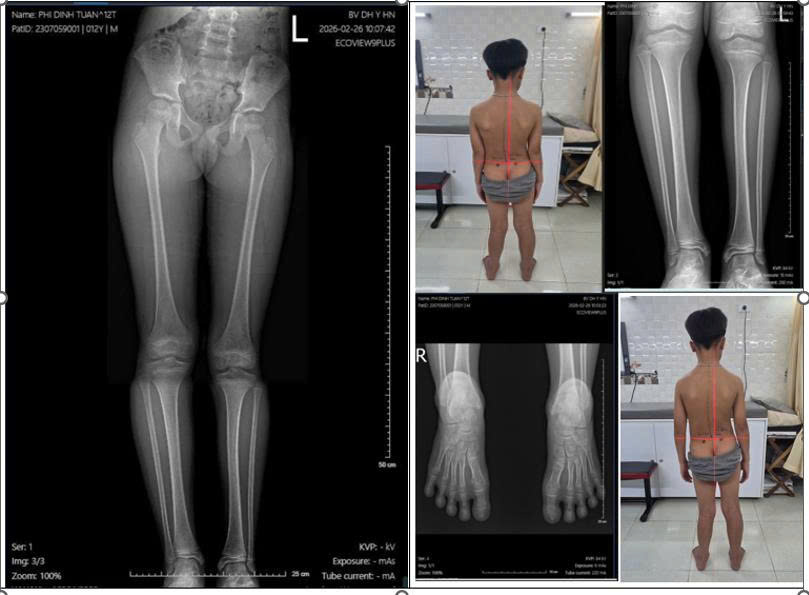

Trước tiên, hãy cùng chúng tôi xem và phân tích một ca cụ thể, điển hình, đang điều trị Bệnh lý bàn chân bẹt với Đế chỉnh hình: Bé trai, Phí Đình Tuân 12 tuổi đến từ Hà Nội.

Hình ảnh 1: Ban đầu- trước khi điều trị: Phim chụp chiều dài hai chi ; Hình ảnh Toàn bộ cột sống và hai chân nhìn từ phía sau. (Phương pháp chữa Bệnh lý Bàn Chân bẹt)

Phân tích Hình ảnh 1: trước khi khám của Đình Tuân, dễ dàng nhận thấy các dấu hiệu đặc trưng nhất của Bệnh lý bàn chân bẹt, cụ thể:

Bàn chân trái bẹt, sập vòm nhiều, lệch trục. Chân và gối xoay trong, chữ X. Kéo theo một bên xương chậu nghiêng và xoay đổ về phía trước. Dẫn đến lệch chi, một bên chân nhìn thấp hơn (ngắn chức năng), nhưng thực chất thì chiều dài xương hai chân vẫn bằng nhau.

=> sở dĩ có sự chênh lệch chi này là do đường gióng của các khớp giữa hai chân không tương đồng, mất thăng bằng, góc và các khớp bị thay đổi tư thế dẫn đến Đứng và đi nghiêng lệch người sang một bên.

Ở độ tuổi 12, ĐìnhTuân đang trong giai đoạn dậy thì. Chân bẹt nhiều, Khung Chậu, cẳng chân, người đều đã nghiêng lệch rõ rệt, và đã bị ảnh hưởng, tác động lên cột sống hình thành cong vẹo cột sống lưng.

(quan sát đèn rọi zaler với đường kẻ đốt sống lưng và đường cắt dưới đầu gối, hai bàn chân)